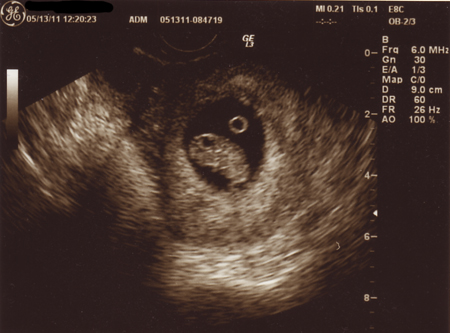

ただいま、推定12週と2日。

チビさんは順調でした。

なんじゃこりゃ?って感じですね(^^;;

頭が左側です。

どっち向いてるんだろう・・・・よくわからないけど。

なんだか、むぎゅーーーって狭そうですね。

違う角度から見ると、手をわしゃって動かしたり、うにうに動いてました。

頭の大きさを測ったのですが、23mmだそうです。

大体週数相応の大きさみたい。

もう、ちっちゃいキューピーちゃん人形ぐらいあるんだね。